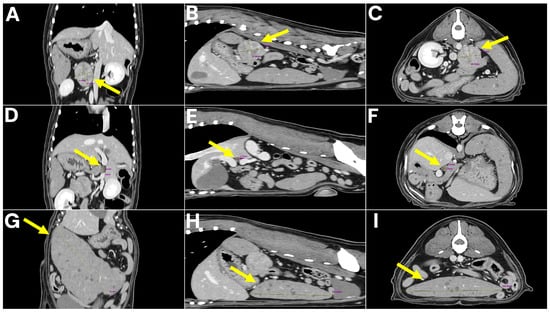

Histopathological examination revealed distinct lesions in the adrenal gland, portal vein, and spleen (Figure 4). The adrenal tumor was composed of polyhedral to pleomorphic neoplastic cells with lightly eosinophilic, finely granular, and often indistinct cytoplasm. The cells were arranged in small lobules or nests along sinusoidal vessels, subdivided by fine fibrovascular septa and capillaries. Areas of coagulative necrosis and hemorrhage were observed throughout the lesions. Immunohistochemically, the neoplastic cells were strongly positive for chromogranin A but negative for cytokeratin and vimentin, consistent with a diagnosis of pheochromocytoma of medullary origin.

Tumor tissue was found adherent to the wall of the PV, morphologically indistinguishable from the adrenal lesion. This finding was interpreted as secondary involvement of the portal vein wall through metastatic spread, rather than direct extension from the adrenal gland. Histologically, the lesion showed pheochromocytoma cells. The tumor cells exhibited the same pleomorphic, polyhedral morphology with finely granular eosinophilic cytoplasm as observed in the adrenal mass.

The spleen showed diffuse replacement of the architecture by large lymphoid cells expanding within the white pulp and compressing the red pulp. Sheets of neoplastic cells formed a characteristic “starry-sky” pattern due to interspersed tingible-body macrophages. The cells consisted of centroblasts with vesicular to coarsely granular chromatin and multiple amphophilic nucleoli, and immunoblasts with a single, centrally located nucleolus. Mitotic figures were often observed. Immunohistochemically, the neoplastic cells were positive for CD20 and negative for CD3, confirming B-cell lineage and supporting the diagnosis of high-grade diffuse large B-cell lymphoma (DLBCL) [14,19]. Examination of mesenteric lymph nodes revealed reactive follicular hyperplasia without evidence of neoplastic infiltration, indicating the absence of metastasis.

Figure 4. Microscopic features of the adrenal tumor, PV wall involvement, and splenic lymphoma. (A) Primary adrenal pheochromocytoma showing tumor nests separated by thin fibrovascular septa, with areas of congestion and multifocal hemorrhage. (B) Higher magnification of adrenal tumor cells exhibiting lightly eosinophilic, finely granular cytoplasm; neoplastic cells range from polyhedral to pleomorphic forms. (C) Tumor tissue adherent to the wall of the portal vein, morphologically consistent with the adrenal pheochromocytoma, indicating secondary vascular wall involvement. (D) Immunohistochemical staining for chromogranin A demonstrating strong labeling of chromaffin granules within adrenal tumor cells. (E) Splenic diffuse large B-cell lymphoma composed of large sheets of centroblasts and immunoblasts with euchromatic nuclei, vesicular or coarsely granular chromatin, and prominent amphophilic nucleoli. (F) Immunohistochemistry of splenic lymphoma showing positive labeling for CD20 in neoplastic B cells.